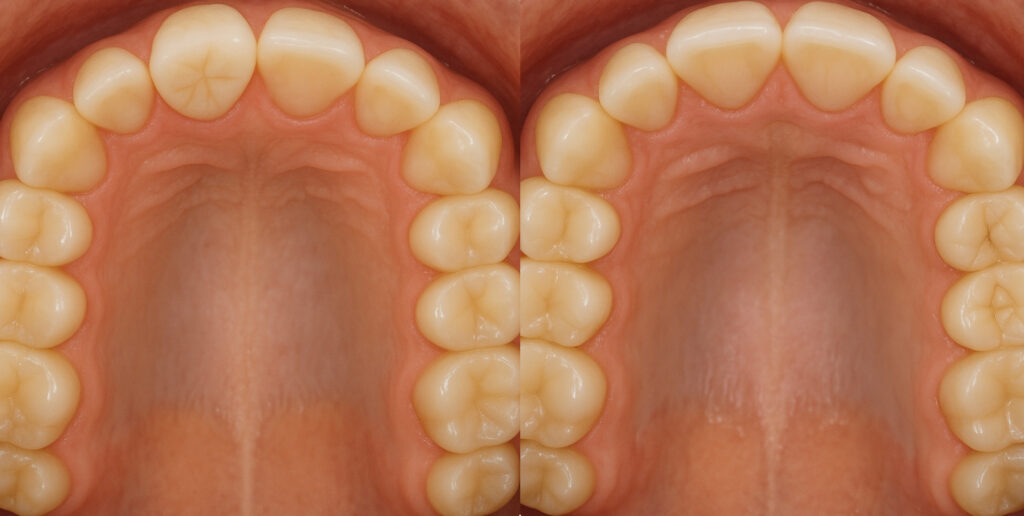

「カマクラデントフェイシャルオーソピディクスオリジナルの取り外しの効くミニマムアクチベータの治療結果」

「子どもの矯正歯科」 「日本歯科専門医機構認定矯正歯科専門医  山本一宏の blog 」 日本歯科専…